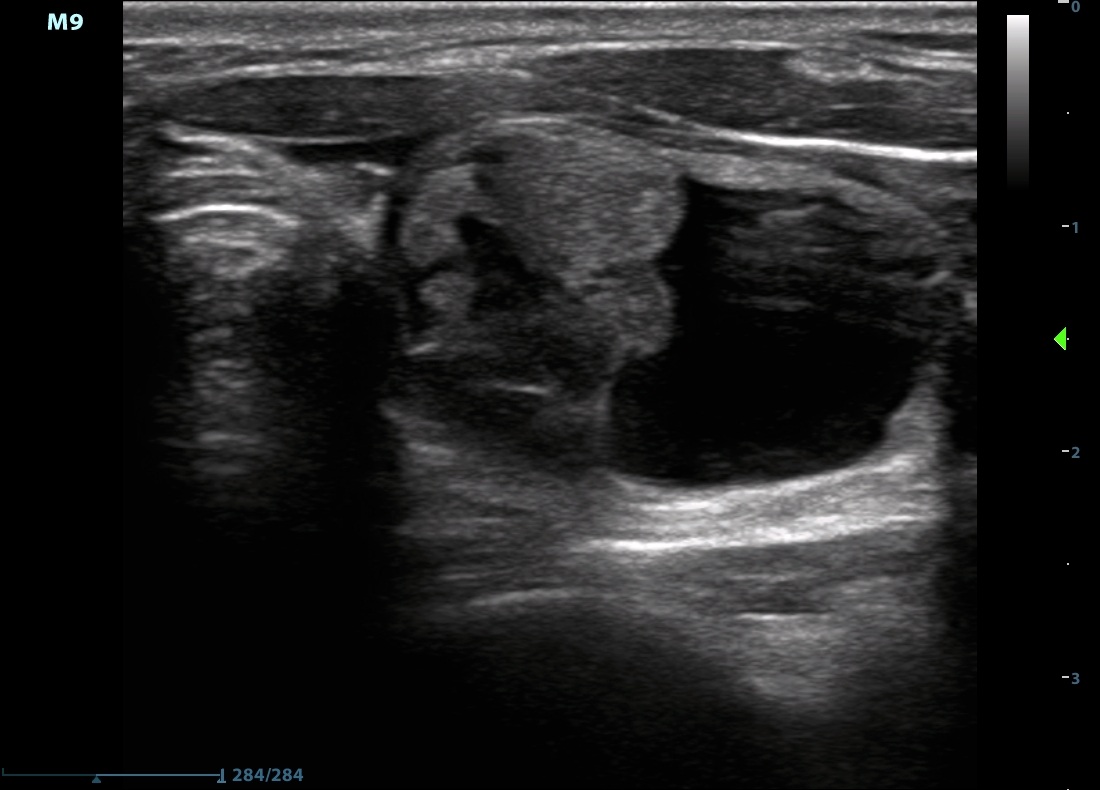

Left lobe horizontal and longitudinal scan

In many instances we cannot clearly categorize a cystic nodule. This nodule presents sings of a spongiform and an eccentric type cyst. Although elastography has no relevance in the event of a cystic nodule, the image demonstrates that the solid part is hard (blue) while the cystic part is soft (green and red).